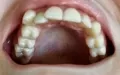

Мне 24 года. С 13-15 лет носила брекеты. В 19 прорезались зубы мудрости, и зубы верхней челюсти стали выступать из зубного ряда. Мучиться с брекетами больше не хочу.

Подскажите, есть ли ещё варианты исправления такой ситуации как у меня, хотя бы эстетически? Может виниры или элайнеры какие?

Конечно нельзя, проблема, действительно, связана с восьмыми зубами, которые необходимо удалить как можно раньше и после обратиться к ортодонту. К сожалению, выпирающий зуб настолько вылез из зубного ряда, что даже обточка и установка коронки в Вашем случае не дадут хороших результатов, да это и неправильно.